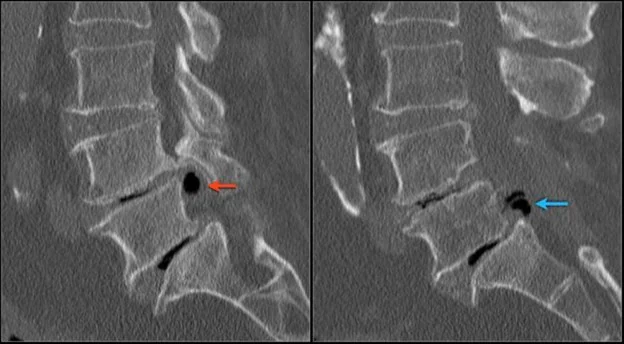

A ressonância magnética é o exame mais indicado. É indolor, sem radiação, e permite visualizar as partes moles em detalhe — sendo o estudo de imagem mais apropriado para o diagnóstico, classificação e diagnóstico diferencial da hérnia de disco lombar.

Ressonância magnética demonstrando hérnia discal volumosa comprimindo o canal vertebral em L4-5

Ressonância magnética demonstrando hérnia discal volumosa e gigante comprimindo o canal vertebral em L4-5 (seta vermelha).

A tomografia computadorizada também é eficaz, porém apresenta menor qualidade de imagem e emite radiação. Deve ser utilizada quando a ressonância não é possível, na suspeita de lesões ósseas associadas, calcificadas ou processos expansivos.